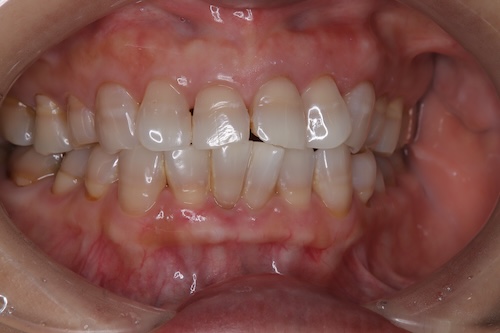

テトラサイクリン歯による着色が見られる40代の女性

- 施術前